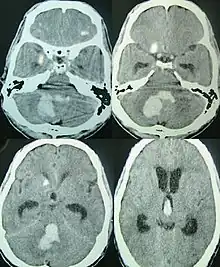

| CT scan of a spontaneous intracerebral bleed, leaking into the lateral ventricles | |

Intraparenchymal hemorrhage can be recognized on CT scans because blood appears brighter than other tissue and is separated from the inner table of the skull by brain tissue. The tissue surrounding a bleed is often less dense than the rest of the brain because of edema, and therefore shows up darker on the CT scan.[20] The oedema surrounding the haemorrhage would rapidly increase in size in the first 48 hours, and reached its maximum extent at day 14. The bigger the size of the haematoma, the larger its surrounding oedema.[21] Brain oedema formation is due to the breakdown of red blood cells, where haemoglobin and other contents of red blood cells are released. The release of these red blood cells contents causes toxic effect on the brain and causes brain oedema. Besides, the breaking down of blood-brain barrier also contributes to the odema formation.[22]